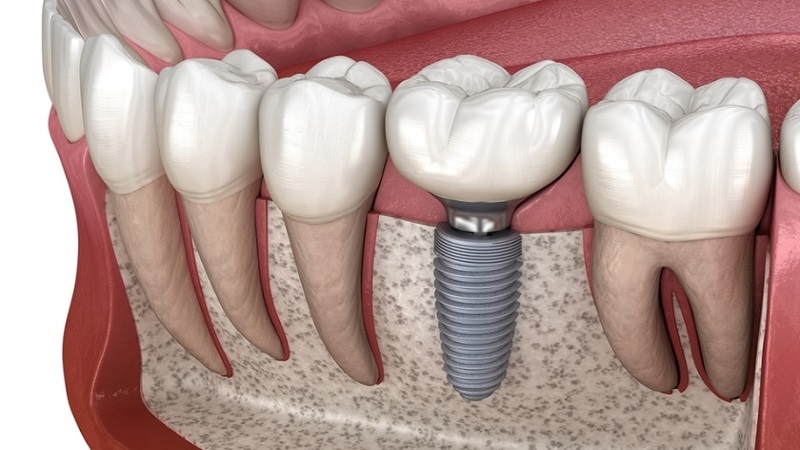

- ایمپلنت دندان اصفهان

مدیریت درد و عفونت با آنتیبیوتیکها و داروهای ضدالتهابی پس از ایمپلنت

مدیریت درد و عفونت با آنتیبیوتیکها و داروهای ضدالتهابی پس از ایمپلنت

کاشت ایمپلنت دندانی، یک سرمایهگذاری هوشمندانه برای بازگرداندن ...